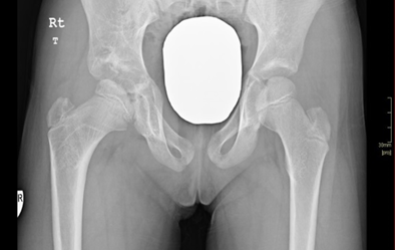

A child treated with a hip spica with hips in a reduced position

Pre-operative

Post-operative